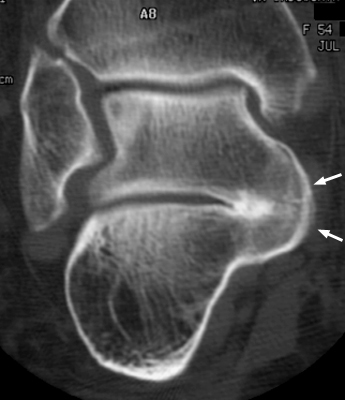

Lateral radiograph of the foot revealing a classic C sign which is a C-shaped line formed by the medial outline of the talar dome and the inferior outline of the sustentaculum tali. This is a sign of subtalar coalition. It is a reliable indicator of subtalar coalition on the lateral radiograph and represents the bony bridge between the talar dome and the sustentaculum tali.

Lateral foot - Click on the image for a larger versionACoronal CT - Click on the image for a larger versionB